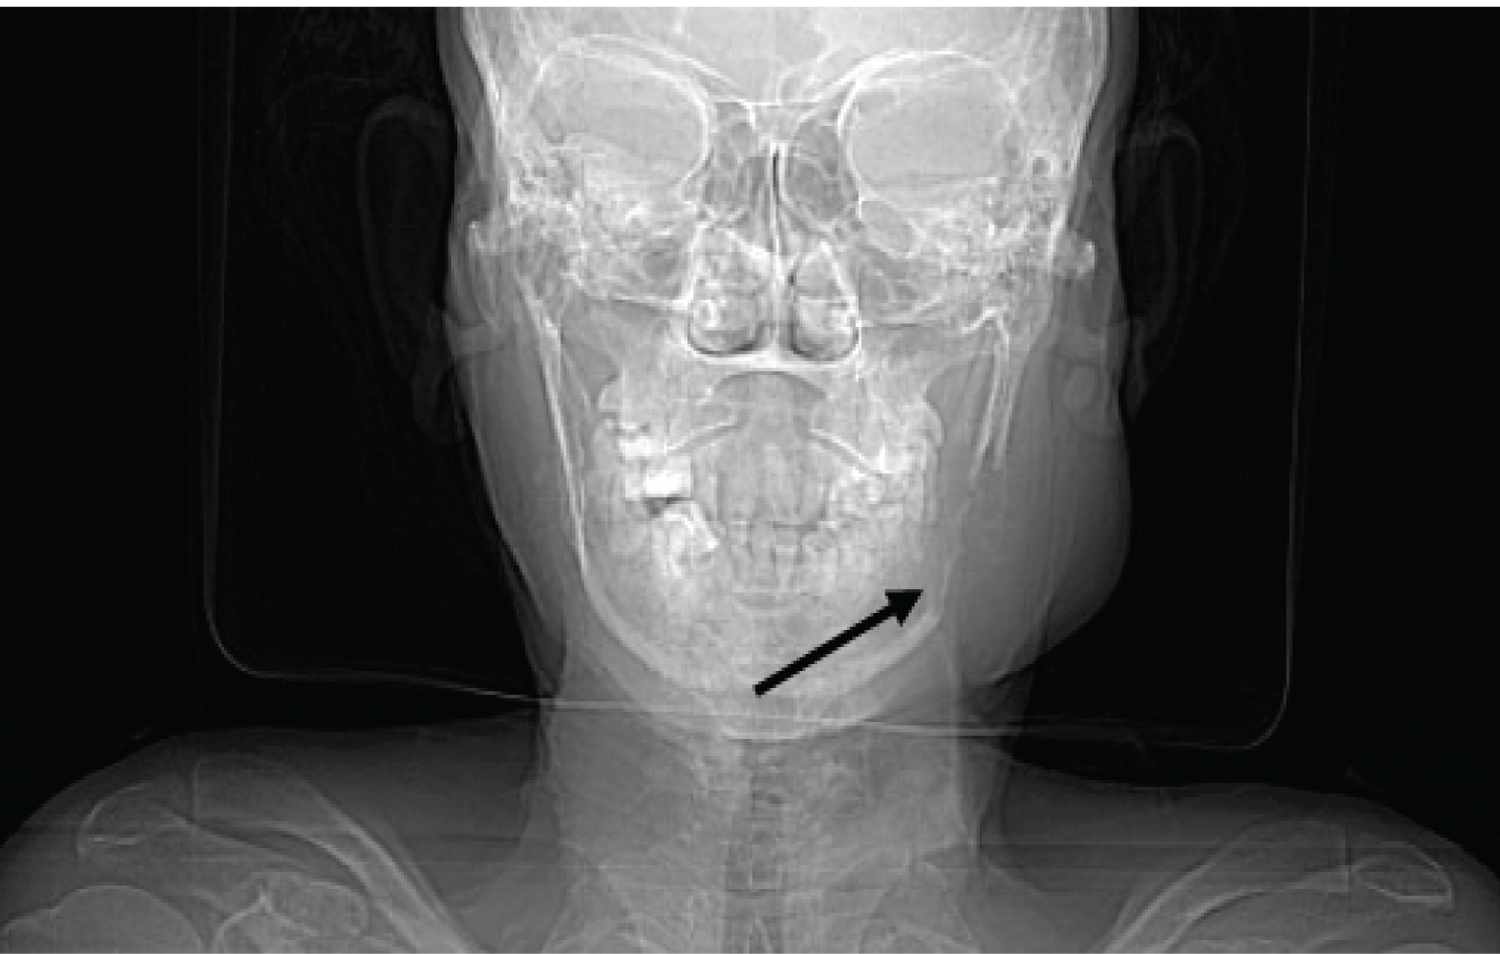

A 57-yr-old female presented to ENT OPD with swelling over the left parotid region measuring 5 × 4 cm of 1 month duration (Figure 1). The patient has been a betel nut chewer for 30 yrs and had consulted with a dentist initially for the swelling and then referred to our center for further evaluation. The swelling was gradually increasing in size with mild dragging pain. She further complained of generalized body weakness and dull aching headache occasionally. Fine needle aspiration was done using a 22 G needle and a 10 cc syringe. Alcohol-fixed smears and air-dried smears were examined with H&E, PAP, and Giemsa staining. Highly cellular smears revealed pleomorphic looking plasma cells with eccentrically placed nuclei with high nuclear cytoplasmic ratio and abundant eosinophilic cytoplasm (Figure 2 and Figure 3). A preliminary diagnosis of plasmacytoma was considered and further work-up was suggested to look for systemic involvement of the disease. Routine blood investigations revealed Hb: 8.5 mg/dl, WBC: 6660 cells/µl and platelet count: 2.13 lakh/µl. Peripheral smear examination revealed a dimorphic blood picture with increased rouleaux formation. ESR was 100 mm/1 st hr. Serum creatinine levels were 3.38 mg/dl and blood urea nitrogen 35 mg/dl. Serum Calcium levels were 13.5 mg/dl and elevated. Meanwhile, an X-ray skull showed multiple lytic lesions and a lytic lesion over the mandible corresponding to the swelling (Figure 4). CT scan further confirmed multiple lytic lesions over the skull and ribs. The urine routine showed trace albumin. Bence Jones protein test on the urine sample was performed and turbidity appeared at 60 °C on heating, dissolved at 100 °C, and reappeared after cooling thereby contributing to the diagnosis. A final diagnosis of multiple myeloma was made after clinical, radiological, and cytological correlation.

Figure 4: CT scan shows lytic lesion over mandible corresponding to the parotid region swelling. View Figure 4